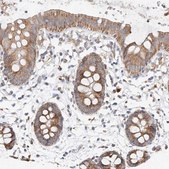

Anti-MRPL24 antibody produced in rabbit

immunohistochemistry: 1:50-1:200, western blot: 0.04-0.4 μg/mL

All Prestige Antibodies Powered by Atlas Antibodies are developed and validated by the Human Protein Atlas (HPA) project and as a result, are supported by the most extensive characterization in the industry.

The Human Protein Atlas project can be subdivided into three efforts: Human Tissue Atlas, Cancer Atlas, and Human Cell Atlas. The antibodies that have been generated in support of the Tissue and Cancer Atlas projects have been tested by immunohistochemistry against hundreds of normal and disease tissues and through the recent efforts of the Human Cell Atlas project, many have been characterized by immunofluorescence to map the human proteome not only at the tissue level but now at the subcellular level. These images and the collection of this vast data set can be viewed on the Human Protein Atlas (HPA) site by clicking on the Image Gallery link. We also provide Prestige Antibodies® protocols and other useful information.

• IHC tissue array of 44 normal human tissues and 20 of the most common cancer type tissues.